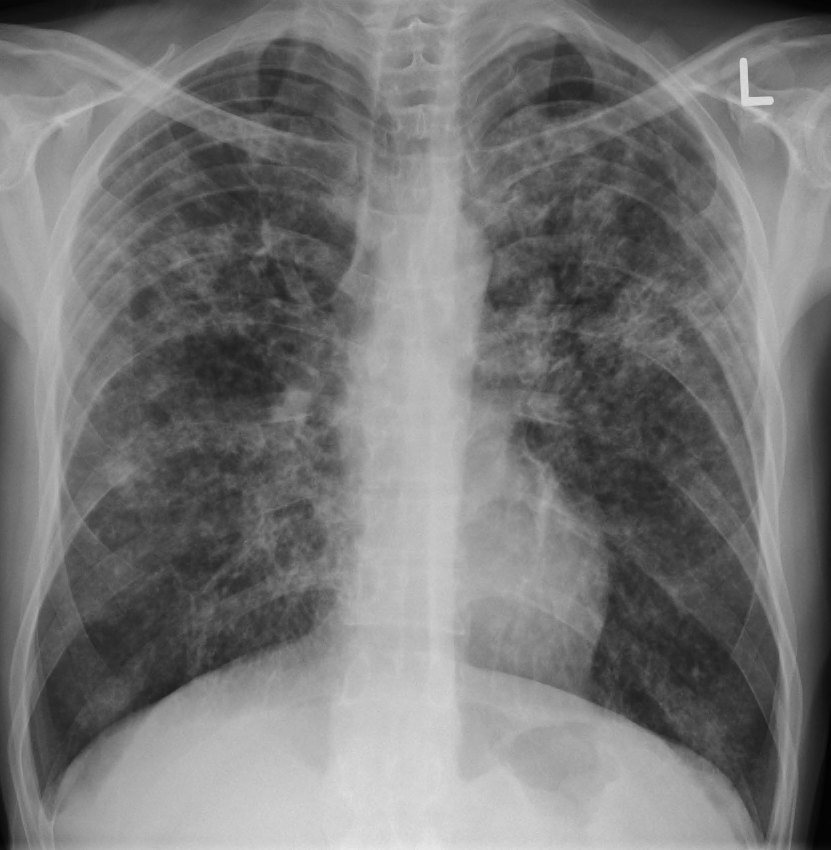

Q.25. Radiological feature for miliary TB is?

Correct Answer : B

The classic radiographic findings of evenly distributed diffuse small 2–3-mm nodules, with a slight lower lobe predominance, are seen in 85% of cases of miliary TB.